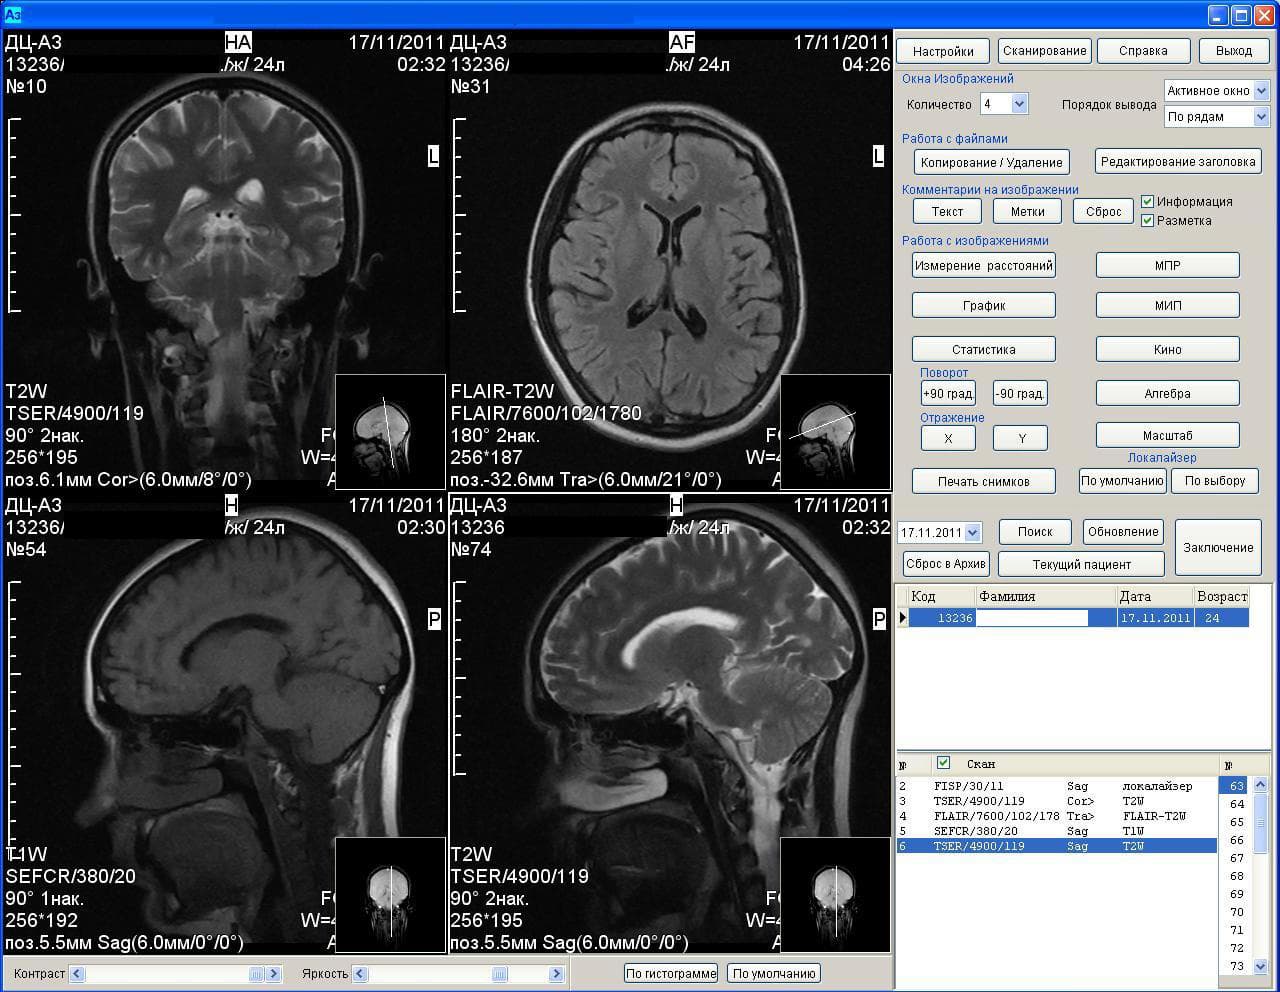

Results of the MRI machine Az-300

It is noted that scientists have restored the functional networks of the brain of healthy people and patients with depression. The technique, named the "consensus approach", revealed differences in the results of functional MRI in two groups of people.

The development of Russian scientists allows with a high degree of accuracy to determine depression. In the near future, BFU specialists plan to create a system for automatic recognition of depression using MRI.